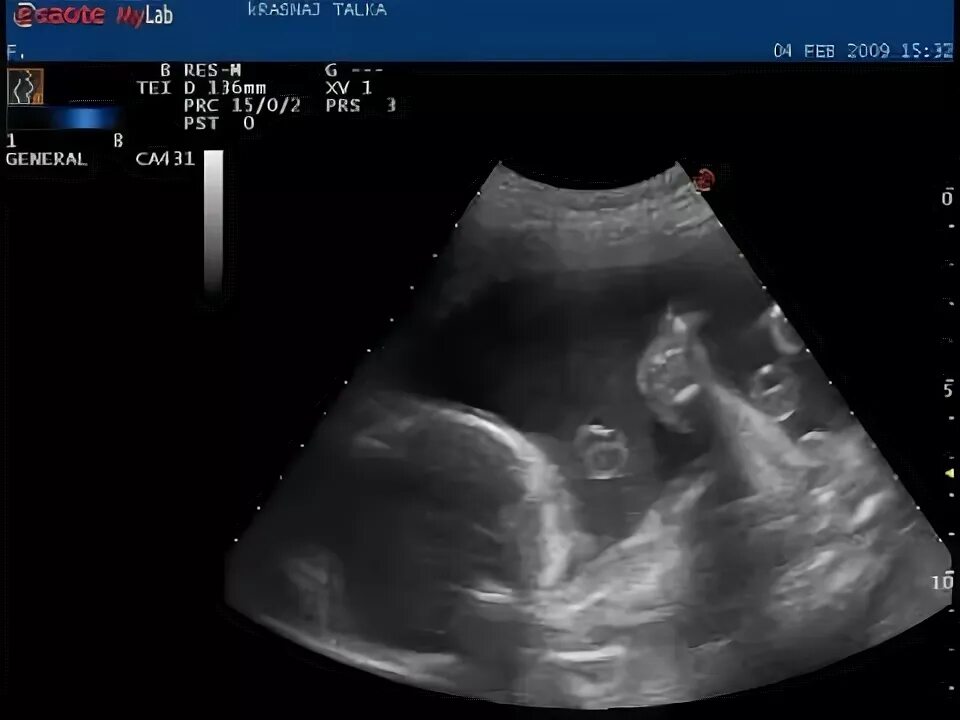

Сейчас 23 недели